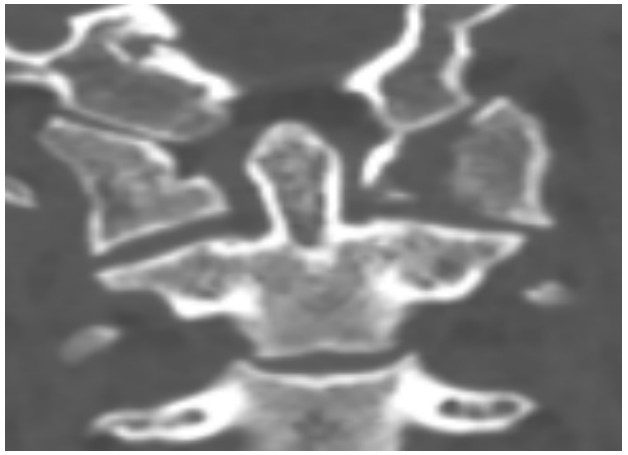

國慶節(jié)前一天,譚女士不幸被門框砸傷頸部,劇烈的疼痛和頸椎的活動受限讓她的世界瞬間陷入了黑暗。在經(jīng)歷了初步的檢查后,譚女士被診斷為寰椎骨折,這個(gè)診斷如同一道晴天霹靂,讓她和家人的心沉入了谷底。絕望中,譚女士被緊急轉(zhuǎn)至衡陽市中心醫(yī)院骨科一區(qū)(脊柱外科),錢軍博士及其團(tuán)隊(duì)在接到這一緊急病例后迅速接診,經(jīng)過細(xì)致的病史詢問、體格檢查和影像學(xué)資料分析,確診譚女士的寰椎骨折伴有寰樞椎體不穩(wěn)定,迫切需要手術(shù)治療以恢復(fù)其穩(wěn)定性??紤]到上頸椎手術(shù)的高風(fēng)險(xiǎn)性,特別是寰樞椎周圍結(jié)構(gòu)復(fù)雜,緊鄰椎動脈和脊髓,手術(shù)過程中的任何微小失誤都可能導(dǎo)致災(zāi)難性后果,錢軍博士團(tuán)隊(duì)頂著壓力,迎難而上,沒有絲毫猶豫,立即行急診手術(shù),投入到緊張的救治工作中。